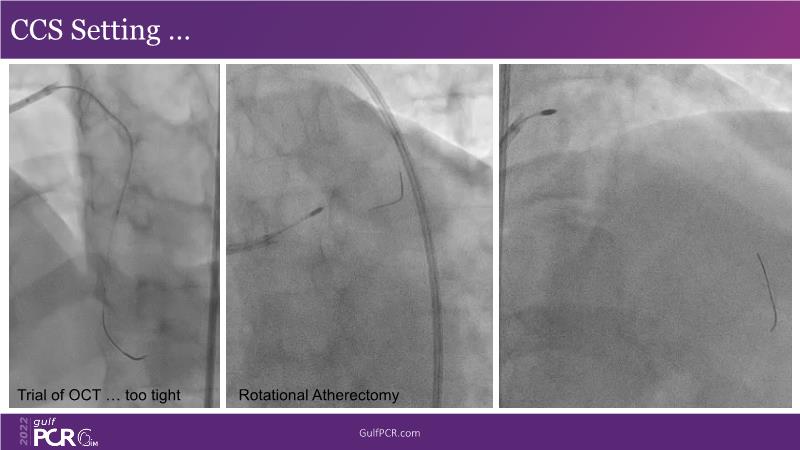

Optimal PCI in patient with long calcified lesion

In this session, follow a LIVE case from the Chest Diseases Hospital in Kuwait and learn what the best strategy is to treat patients who present with a very long calcified coronary artery lesion, as well as how to select the best device and which different types of stents can be used.

- To learn correct interpretation of a long-calcified lesion and how to adopt procedural strategy